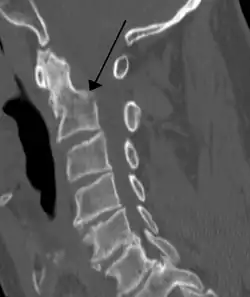

Teardrop fracture of C3 (sagittal CT)